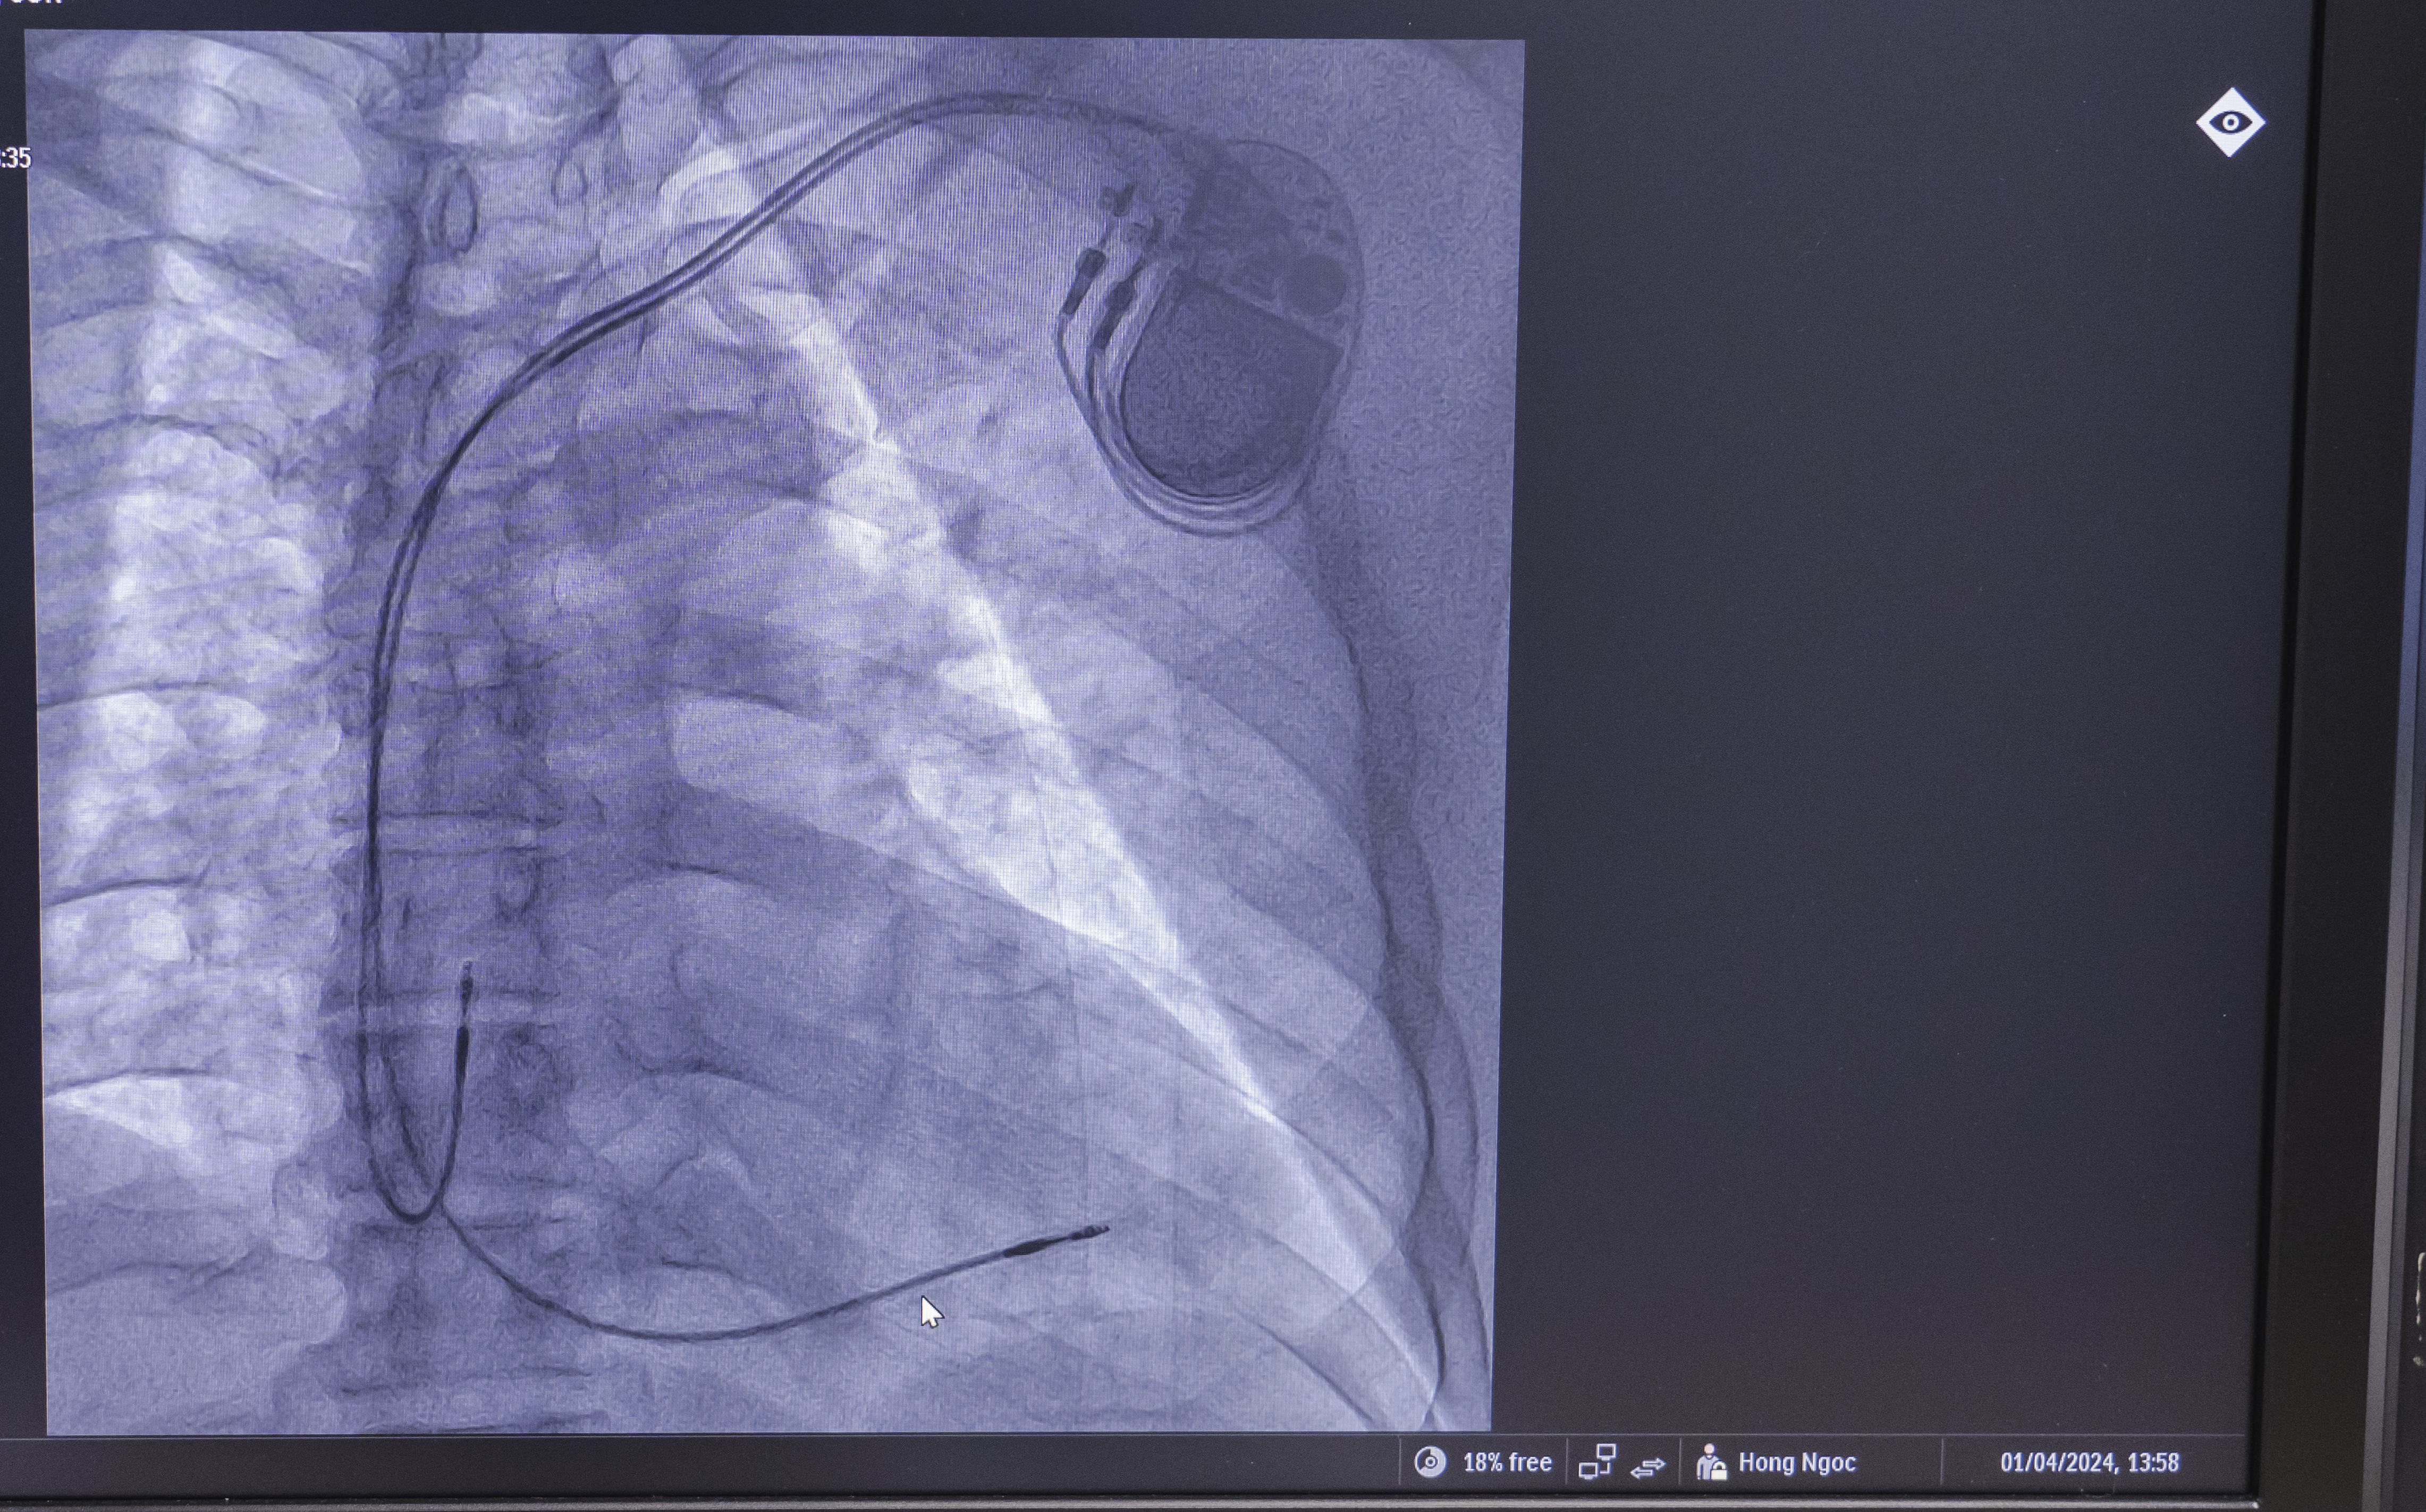

- Máy tạo nhịp tim hai tâm thất: Thiết bị này dành cho những người bị suy tim và nhịp tim không đều giúp kích thích cả hai buồng tim dưới (tâm thất phải và trái) để tim đập tốt hơn.

Máy tạo nhịp tim được đặt dưới vùng ngực để kiểm soát nhịp tim cho bệnh nhân

- Máy khử rung tim cấy ghép (ICD: Theo dõi nhịp tim và gây sốc điện nếu phát hiện thấy nhịp tim không đều (loạn nhịp tim) do bệnh cơ tim giãn gây ra.